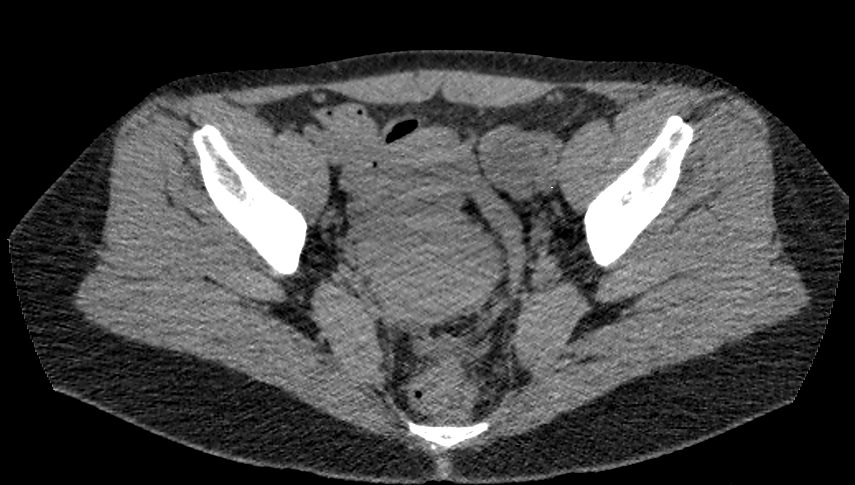

Методика КТ позволяет оценить анатомическое строение почек, надпочечников, состояние мочеточников и мочевого пузыря, кроме того, дает возможность визуализировать сосудистую систему и регионарные лимфатические узлы.

Сканирование применяется для выявления воспалительных заболеваний почек, чашечно-лоханочной системы, мочеточников и мочевого пузыря, также позволяет обнаружить конкременты на фоне мочекаменной болезни, диагностировать доброкачественные и злокачественные новообразования, точно классифицировать кистозные образования по системе Bosniak, что особенно важно для урологов и нефрологов, а также определить степень поражения регионарных лимфатических узлов. Кроме того, КТ используется для диагностики травматических повреждений органов мочевыделения, аномалий развития почечно-лоханочной системы, дает максимальную информацию для хирурга при планировании оперативного вмешательства.

Что показывает КТ почек, мочеточников, мочевого пузыря

- опущение почек;

- аномалии развития почек, мочетоников

- доброкачественные и злокачественные новообразования;

- камни (конкременты);

- уретероцеле

- сосудистую патологию (сосудисто-мочеточниковый конфликт, инфаркт почки);

- последствия оперативных вмешательств;

- увеличение лимфоузлов в брюшной полости, забрюшинном пространстве и малом тазу;

- травматические изменения

- патологии сосудов малого таза.